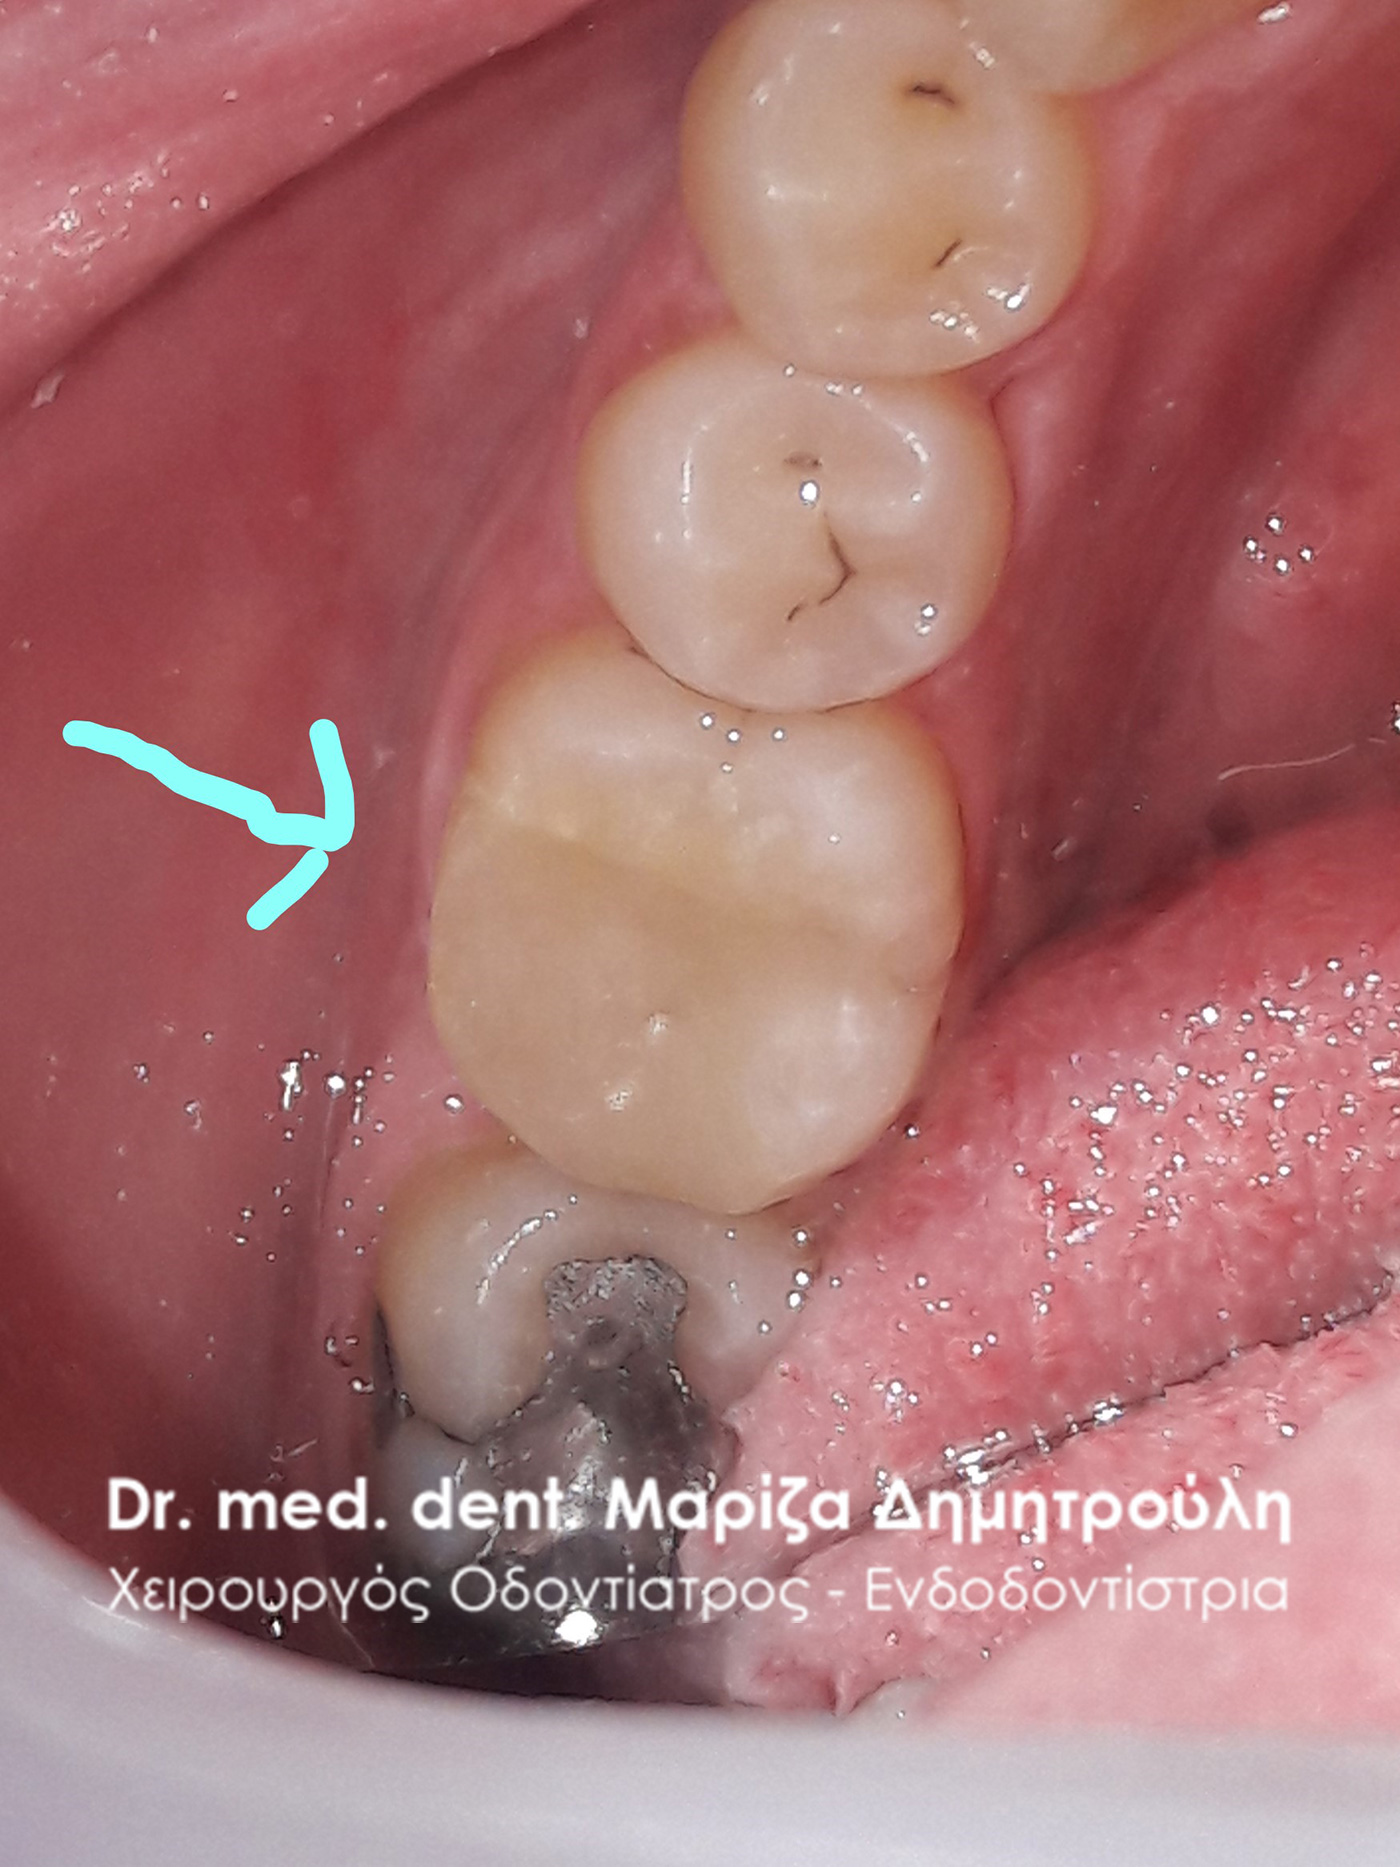

Removal of amalgam (silver) filling

BEFORE

AFTER

AFTER